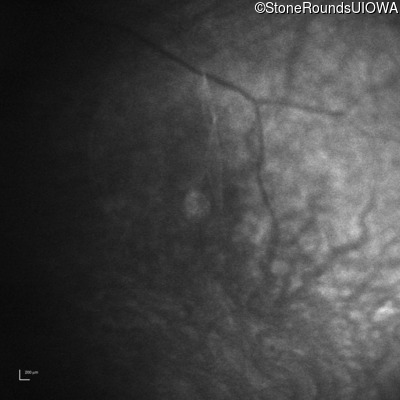

Infrared Fundus Photograph - Left -

No Light Perception

Exemplar

Expanded OCT Stack

×